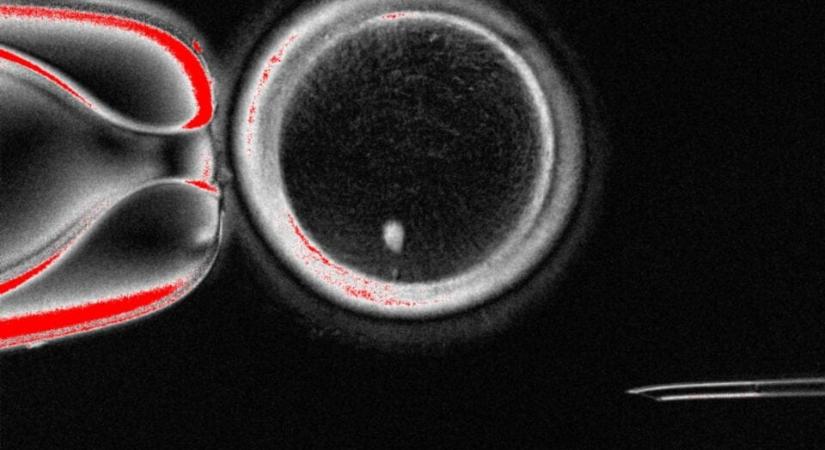

Úgy tűnik, tényleg át lehet programozni az emberi bőrsejteket úgy, hogy azok laboratóriumi körülmények között megtermékenyíthető petesejtek legyenek.